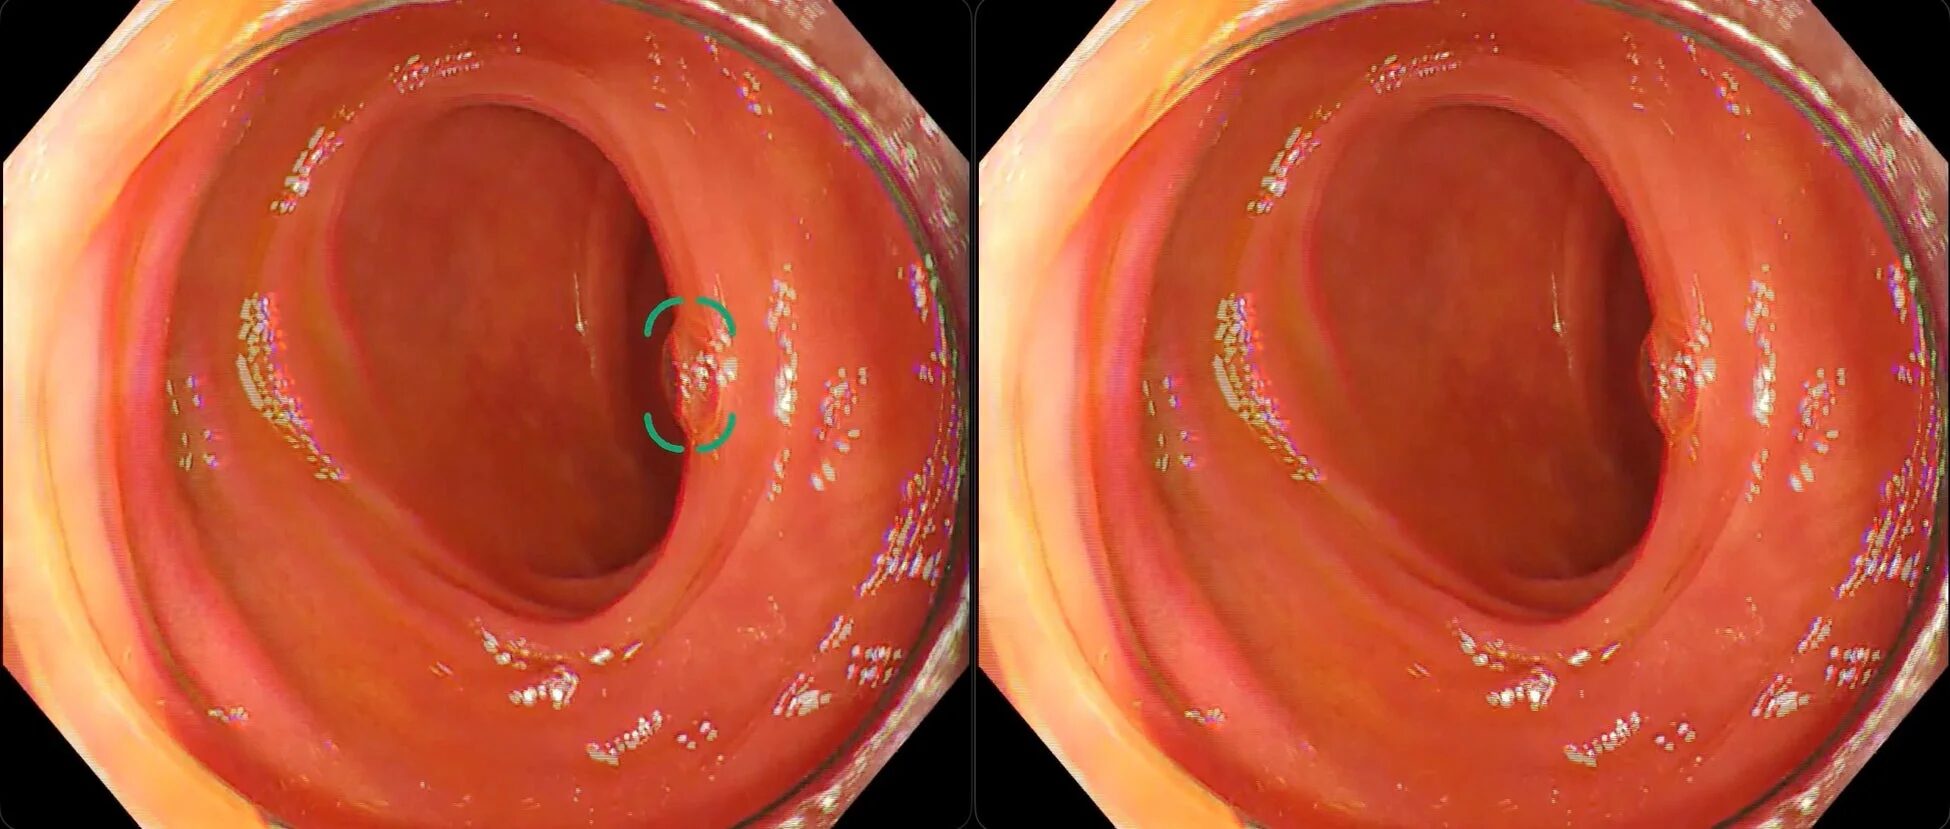

新モデルがどれだけ賢くなったのか、具体的な検出事例を見てみましょう。特に、これまで偽陽性の原因となっていた「残渣」「ひだ」「泡」による誤検出が改善されている点が注目されます。

③ 泡による偽陽性が改善した例

消化液の泡も、内視鏡検査では誤検出の原因の一つでした。新モデルでは、泡とポリープをしっかりと区別できるようになり、より正確な検出が可能になりました。

これらの改善により、医師は本当に注目すべきポリープ候補に集中でき、検査の質と効率が大きく向上することが期待されます。